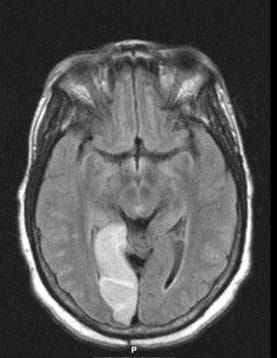

Neuroradiology and PACS NeuroimagingOur Department has a close working relationship with the Division of Neuroradiology within the Department of Radiology.

There are eight full-time neuroradiologists. Within their division is a strong group of endovascular specialists who work closely with the brain attack team and vascular neurologists. Intra-arterial TPA, coiling of aneurysms, mechanical thrombectomy, extracranial and intracranial stenting and other cutting-edge procedures are routinely employed.

Neuroradiology and PACS NeuroimagingIn addition, one of the major conveniences of the neurology residency training program is the system-wide implementation of the Picture Archiving Communications Systems (PACS) digital imaging system at the University Hospitals.

As soon as a scan is completed, it is immediately available to be reviewed electronically. No longer do residents need to spend time looking for lost films or walking to the radiology department to view scans.

Scans are now easily viewed during conferences and rounds. Large, high-resolution monitors are available on all hospital units. Viewing is also easily performed on any computer monitor in the hospital and outpatient clinic.